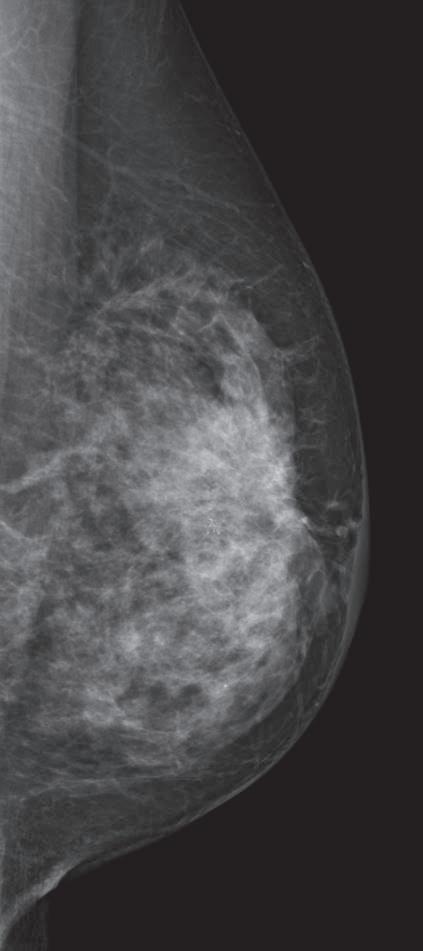

NO MAKING UP FOR LOST TIME Impacts of the Pandemic Lapse in Breast Cancer Screening

At the best of times, bringing at-risk and underserved patients in for routine breast cancer screening can be a complex proposition. But during the novel coronavirus (COVID-19) pandemic, when elective imaging procedures were shelved as all of the health care world shifted to battling the virus, a new wrinkle emerged.

A pre- and post-COVID (March 2019 through May 2021) analysis of the U.S. National Mammography Database pub

lished in the Journal of the American College of Radiology (ACR) in August 2022 identified the impact of these shutdown. Screening mammograms were down 37 percent, diagnostic mammograms down 58 percent, breast biopsies down 47 percent, and cancer diagnoses down 49 percent, all as com pared with pre-pandemic levels.

“Although diagnostic mammogram levels returned to near pre-pandem ic levels … screening mammograms, breast biopsies and, most importantly, cancer diagnoses continue to lag,” wrote Dr. Lars Grimm of the ACR Na

tional Mammography Database (NMD) Committee in a summary.

“These findings are likely to have a major impact on future breast cancer outcomes,” Grimm wrote. “The cancer diagnosis deficit that started in the acute phase of the pandemic continues to grow in parallel with lower screening mammog raphy utilization rates. Failure to diagnose smaller, screen-detected cancers will lead to more late-stage cancers in the future. Initial cancer registry data demonstrates a stage shift to later-stage breast cancers, and multiple modeling studies predict a corresponding increase in patient mor

bidity and mortality.”